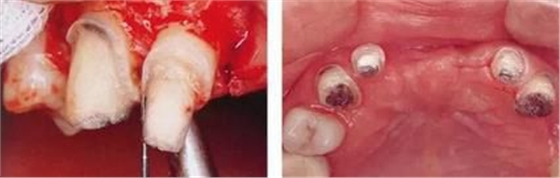

▲圖7-1

對(duì)上頜前牙進(jìn)行初期治療后的咬合面觀。右上2,3存在炎癥。

▲圖7-2,3

▲圖7-2 齦瓣剝離后,可以看到右上3近中側(cè)沉積著大量牙結(jié)石。由于牙根接近而無(wú)法用刮匙除去

▲圖7-3 牙周外科處理后的愈合期狀態(tài)。右上2,3之間愈合形成了充分的角化齦。